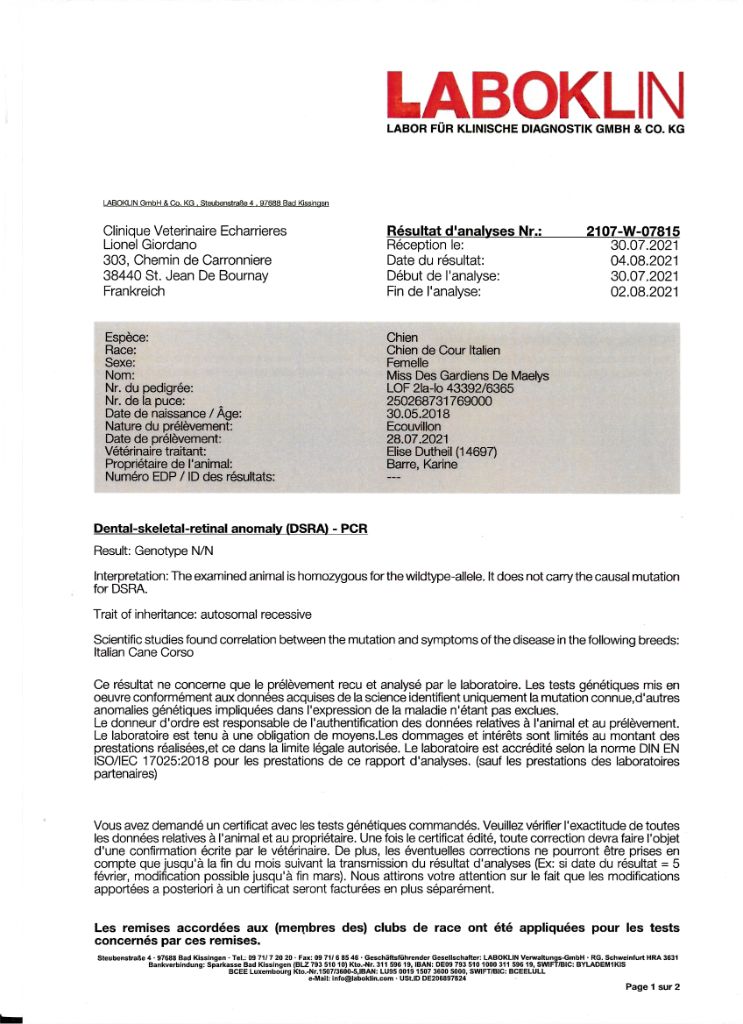

DRSA N/N

DRSA N/N

| Couleur | froment masque gris / DNA/ HD B / ED O / DRSA N/N |